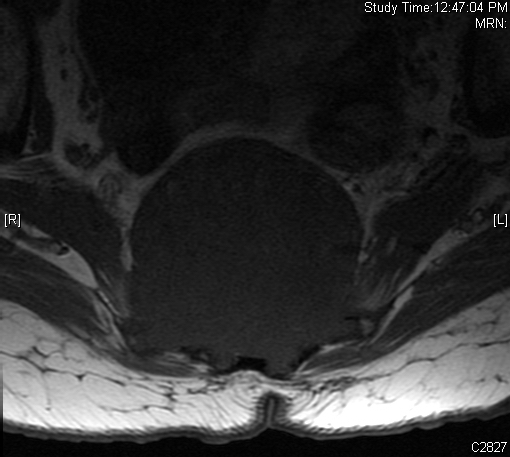

MRI (Fig. 4-10)

• Destructive bone lesion

• Isointense or hypointense on T1W (Fig. 4-5)

• Hyperintense on T2W (Fig. 8 & 9)

• Hyper enhancement with gadolinium (Fig. 6 & 7).

Fig. 4-10: MR image of a chordoma shows a destructive bone lesion in the sacrum that is hypointense on T1W images, hyperintense signal on T2W and enhancement of the lesion after gadolinium.